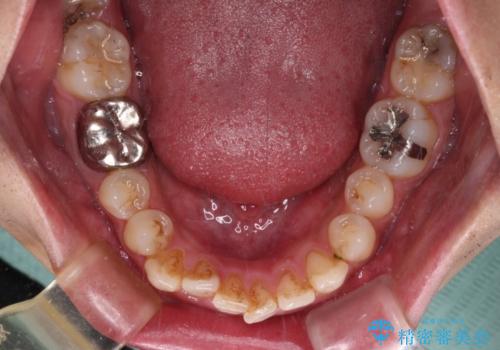

前歯のデコボコと突出感をマウスピース矯正できれいに

- 上下前歯のデコボコと突出感を気にして来院された患者様です。

目立たない装置を希望されたため、インビザラインによるマウスピース矯正を行うこととしました。

矯正治療後に銀歯をセラミックに替えたいとの要望があり、概ね歯列が整ったところで銀歯をセラミックに替え、仕上げにインビザライン1セットを使用して最終的に歯列を整えました。